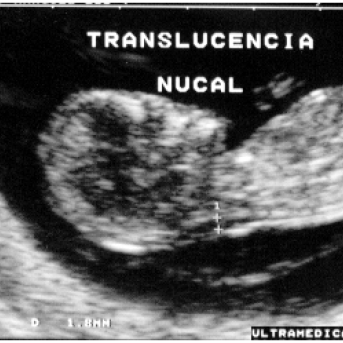

Esse é um exame muito importante para os fetos e mamães pois é ele que detecta possíveis alterações nos bebês como síndrome de Down, síndrome de Patau, Síndrome de Edwards e inúmeros outros problemas que possam a vir acontecer na... Continuar LendoEsse é um exame muito importante para... Continuar Lendo